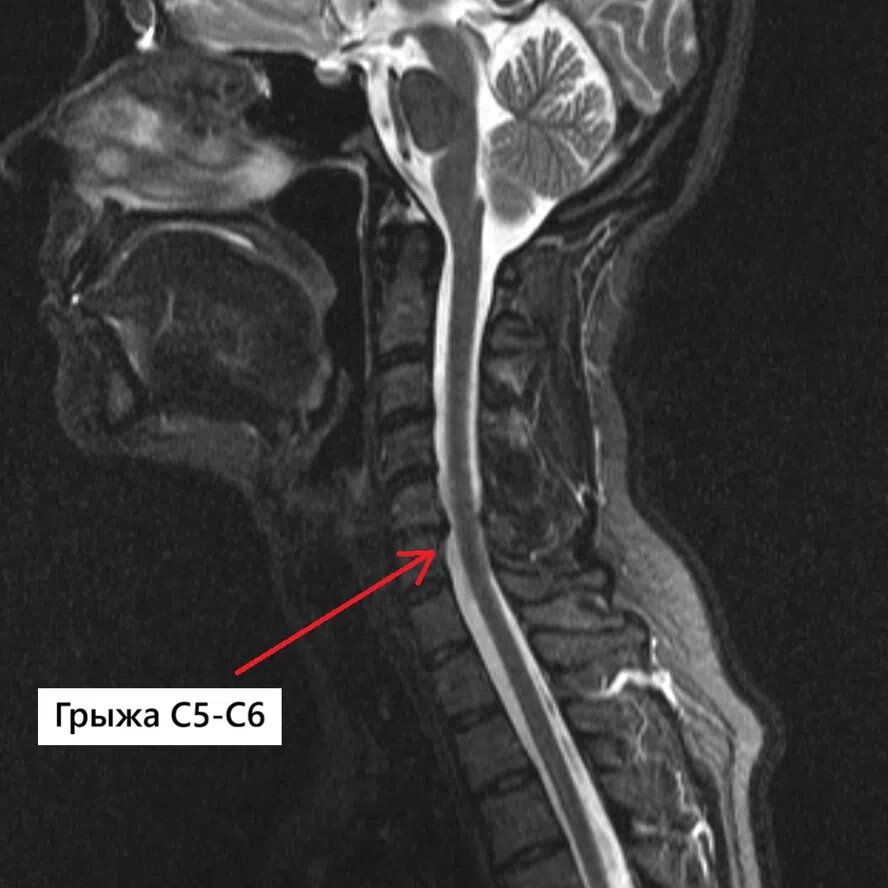

🩻 По Ρ€Π΅Π·ΡƒΠ»ΡŒΡ‚Π°Ρ‚Π°ΠΌ МРВ шСйного ΠΎΡ‚Π΄Π΅Π»Π° ΠΏΠΎΠ·Π²ΠΎΠ½ΠΎΡ‡Π½ΠΈΠΊΠ° выявлСна:Β

Π΄ΠΎΡ€Π·Π°Π»ΡŒΠ½Π°Ρ правосторонняя ΠΏΠ°Ρ€Π°ΠΌΠ΅Π΄ΠΈΠ°Π½Π½ΠΎ-Ρ„ΠΎΡ€Π°ΠΌΠΈΠ½Π°Π»ΡŒΠ½Π°Ρ Π³Ρ€Ρ‹ΠΆΠ° диска Π‘5–Б6 (ΠΏΠΎ Ρ‚ΠΈΠΏΡƒ экструзии) Ρ€Π°Π·ΠΌΠ΅Ρ€ΠΎΠΌ 0,4 см.Β

Π“Ρ€Ρ‹ΠΆΠ° Π΄Π΅Ρ„ΠΎΡ€ΠΌΠΈΡ€ΡƒΠ΅Ρ‚ ΠΏΡ€ΠΈΠ»Π΅ΠΆΠ°Ρ‰ΠΈΠ΅ ΠΎΡ‚Π΄Π΅Π»Ρ‹ Π΄ΡƒΡ€Π°Π»ΡŒΠ½ΠΎΠ³ΠΎ мСшка ΠΈ распространяСтся Π² ΠΌΠ΅ΠΆΠΏΠΎΠ·Π²ΠΎΠ½ΠΊΠΎΠ²Ρ‹Π΅ отвСрстия, суТивая ΠΈΡ…, прСимущСствСнно справа (ΠΏΠΎΠΊΠ°Π·Π°Π½ΠΎ Π½Π° фотографиях).

Π‘Π°Π³ΠΈΡ‚Ρ‚Π°Π»ΡŒΠ½Π°Ρ проСкция